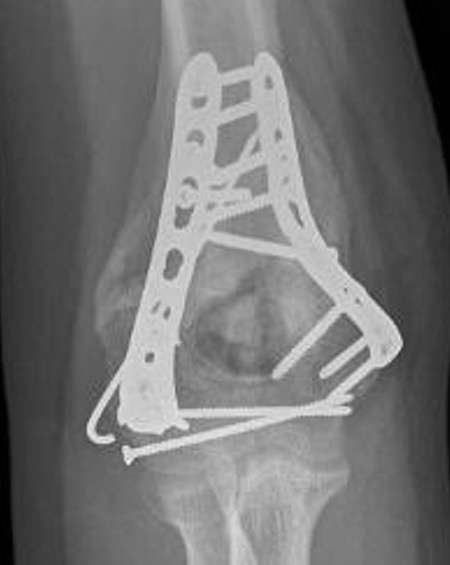

Fixation techniques

Options

Precontoured anatomical plates

Parallel plates v perpendicular plates

Locking v non locking screws

Parallel v perpendicular plates

Parallel plates - medial plate on medial column and lateral plate on lateral column

Perpendicular plates - plates at 90 degrees, with lateral plate posterior

- cadaveric model

- biomechanical superiority of parallel plates versus perpendicular plates

- systematic review of 83 studies and 2362 patients

- parallel plating lower incidence of revision for fixation failure (1% v 6%)

- perpendicular plating reduced overall complication (45% v 54%)

- these complications included lower incidence neuropathy, wound dehiscence, and implant prominence